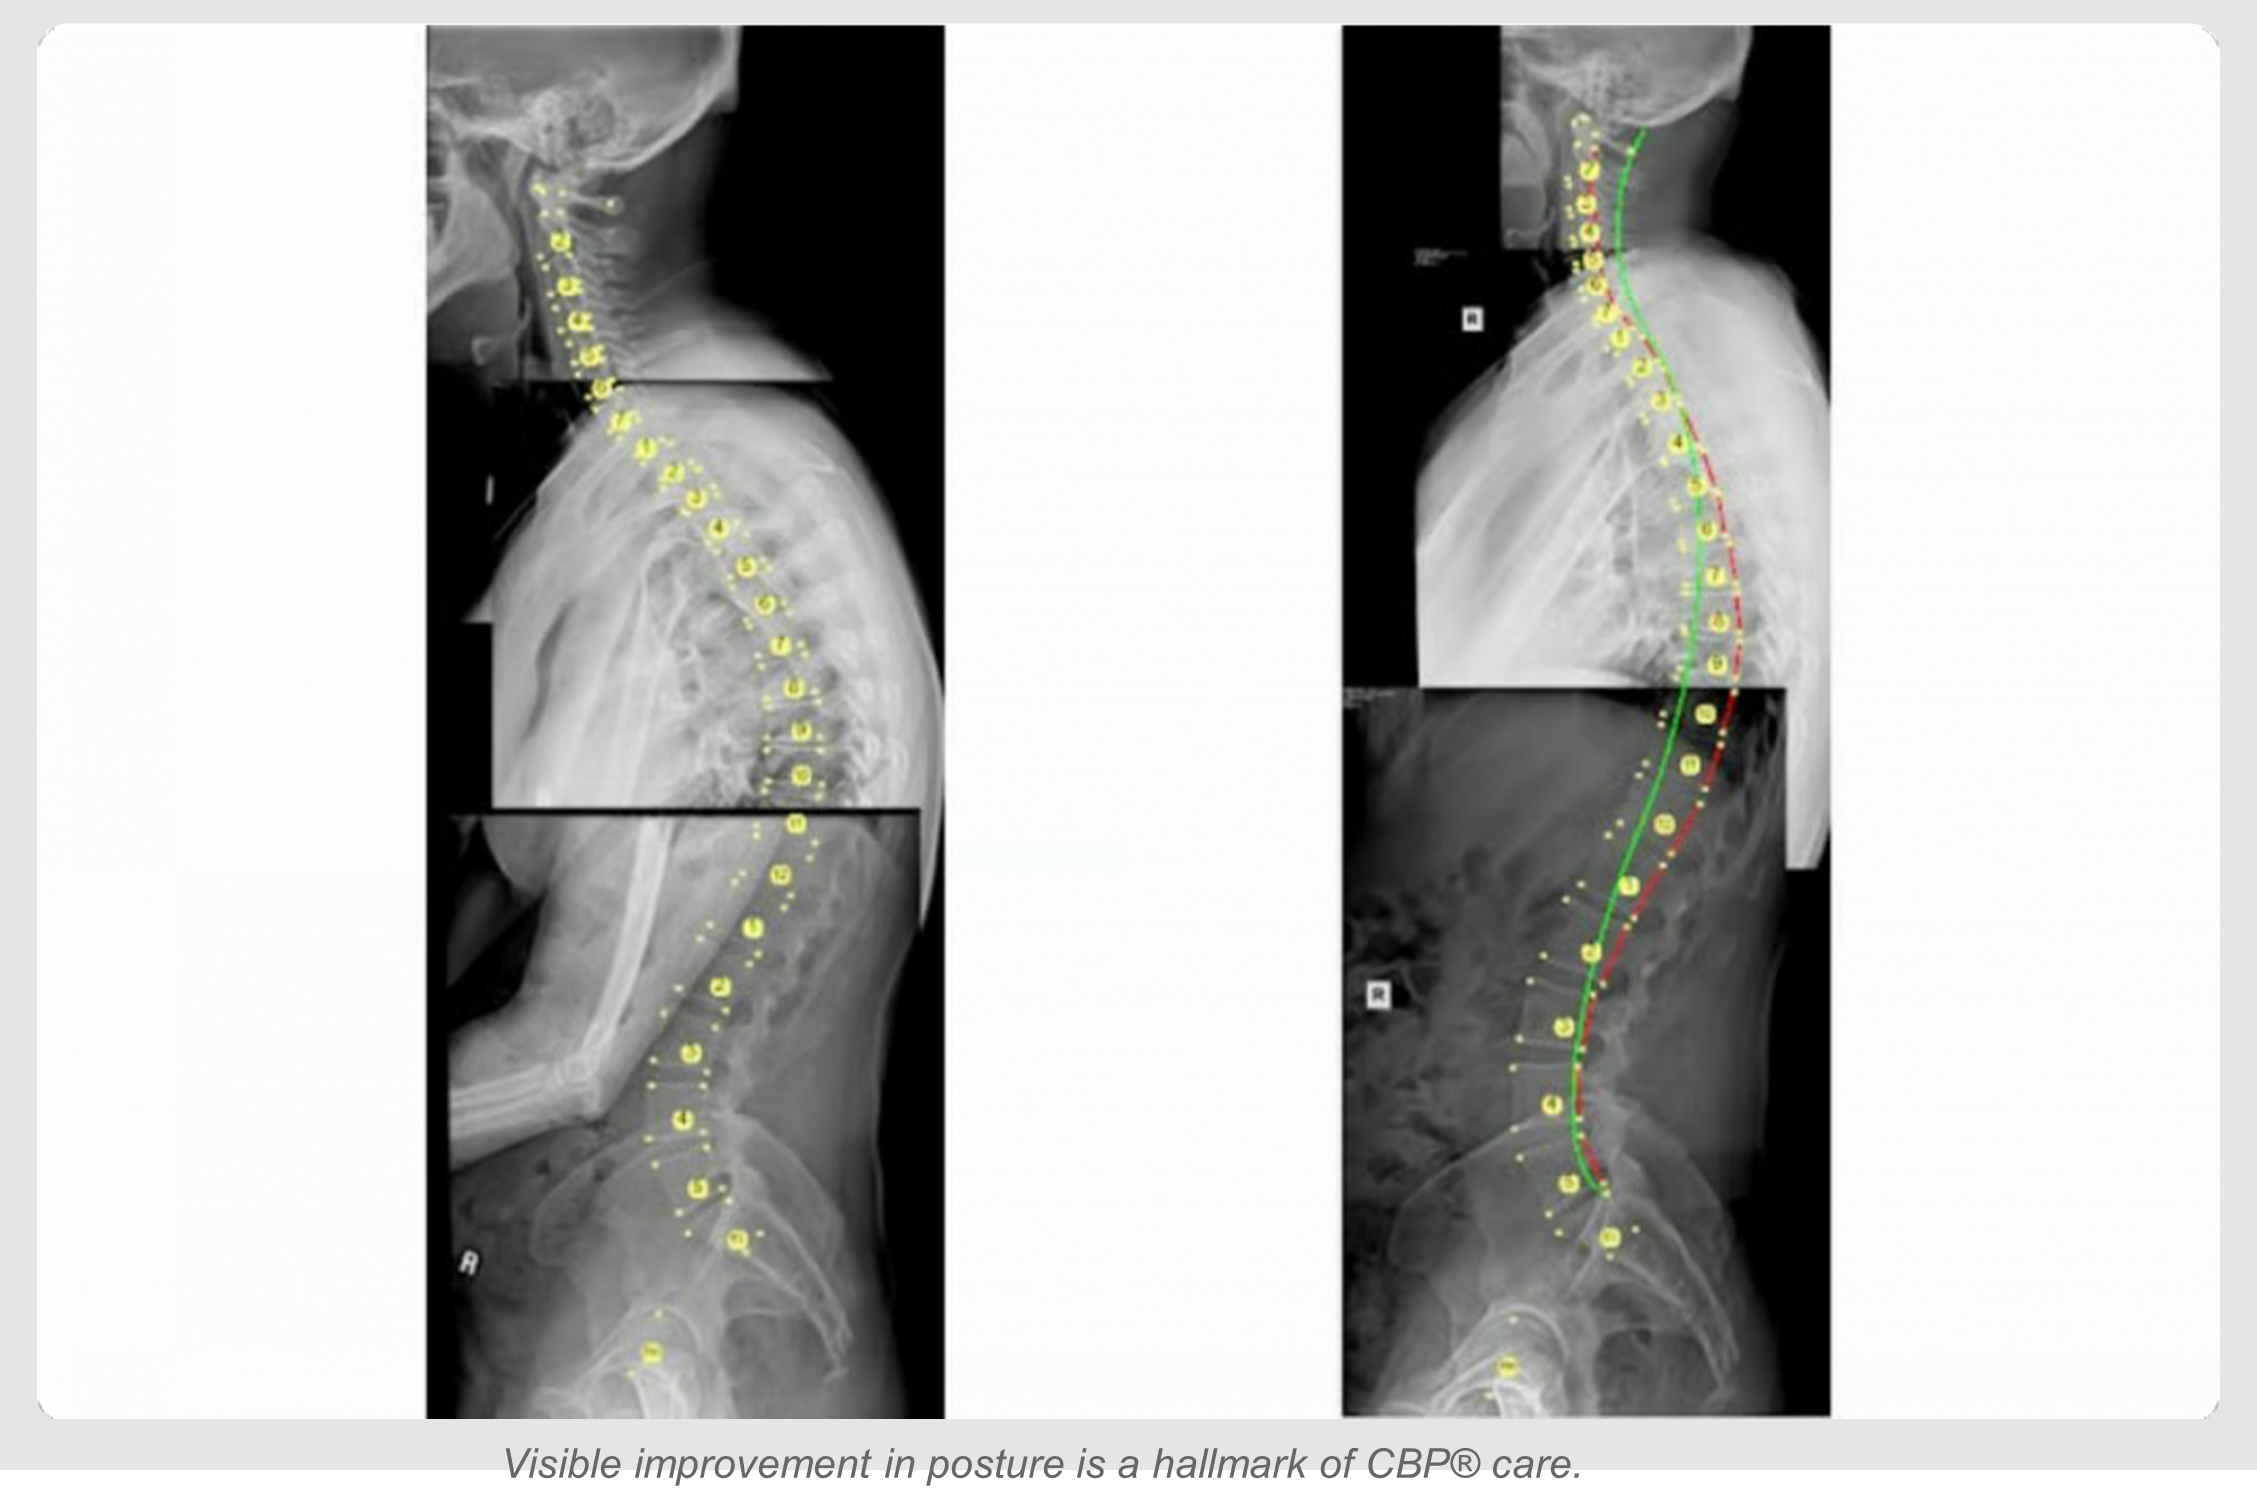

A groundbreaking case study published in the Journal of Physical Therapy Science demonstrates that severe postural deformities—often dismissed as permanent—can be corrected without surgery. Using the multimodal Chiropractic BioPhysics® (CBP®) protocol, a 27-year-old patient achieved an 11.6° reduction in thoracic kyphosis and a massive 93% correction of posterior thoracic translation over just 6 months. These structural changes correlated with the complete resolution of vertigo and upper back pain, alongside dramatic improvements in quality of life.

Radiographic analysis revealed a severe 67° thoracic kyphosis and a significant -51.4mm posterior thoracic translation (backward displacement of the upper torso relative to the pelvis). She also exhibited a lateral shift of the spine and a leg length inequality.

After 30 visits over 6 months, follow-up X-rays and assessments revealed dramatic improvements that far exceeded typical physical therapy outcomes.

| Measurement/Symptom | Baseline (Before) | Outcome (After 6 Months) | Change |

|---|---|---|---|

| Thoracic Kyphosis | 67° (Severe) | 55.4° (Improved) | 11.6° Reduction |

| Post. Thoracic Translation | -51.4 mm | -3.7 mm | 93% Correction |

| Lateral Spine Shift | 12.4 mm | 1.3 mm | Near Complete Correction |

| Oswestry Disability Index (ODI) | 44% (Severe Disability) | 8% (Minimal Disability) | 36 Point Improvement |

| Neck Disability Index (NDI) | 30% (Moderate Disability) | 8% (Minimal Disability) | 22 Point Improvement |

| Vertigo & Upper Back Pain | Severe / Constant | 0/10 (None) | 100% Resolution |

This case challenges the prevailing notion that adult spinal deformities are fixed or progressive. It demonstrates that with the correct application of biomechanical principles—specifically the Mirror Image® traction protocols unique to CBP®—significant structural correction is achievable. For the patient, this meant avoiding the potential need for future surgery and reclaiming an active, pain-free life.